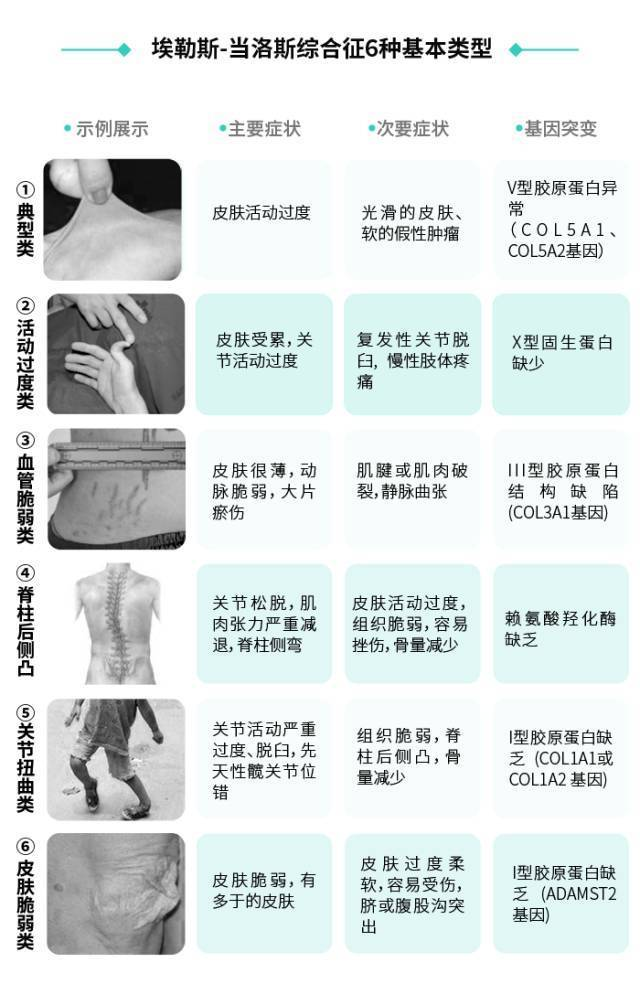

- 注意上面说到的不同程度,这意味着有的患者症状较轻,有的患者症状较重。按照病症和基因突变类型,埃勒斯-当洛斯综合征大概可以分为6种基本类型:

- 前三种呈常染色体显性遗传,后三种呈常染色体隐性遗传,大约有 90 % 90\% 90% 的患者都属于前两种类型,虽然会存在某些异样,但不至于影响到正常的生活,也不会危及生命。